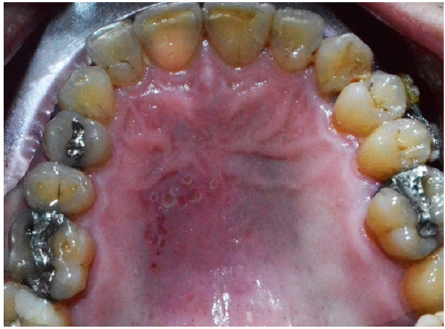

Cluster of punctate red lesions were found on the left half of the patient’s hard palate (Figure1). Further questioning revealed that the patient used to have many lesions in his oral cavity at different occasions and that this has been going for a long period of time. Other lesions were occurring in different areas of his mouth with differences in shapes and sizes. Some of them presented with large white ulcerative areas of few millimetres accompanied with severe pain.

Figure 1:Cluster of punctate red lesions on the left half of the hard palate (picture mirrored during photography).